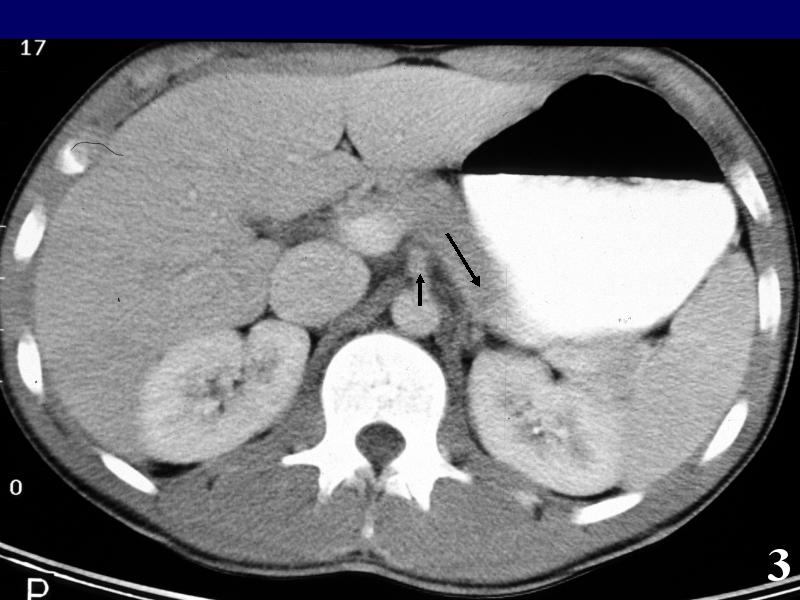

MS 190 CT 14